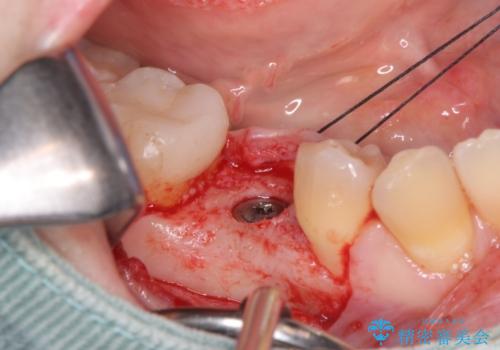

- 過去に抜けてしまった歯のところにインプラントを入れたいとの事で来院。

CTで確認したところ骨の高さや厚みがインプラント埋入できる状態でしたのでインプラント治療を行いました。